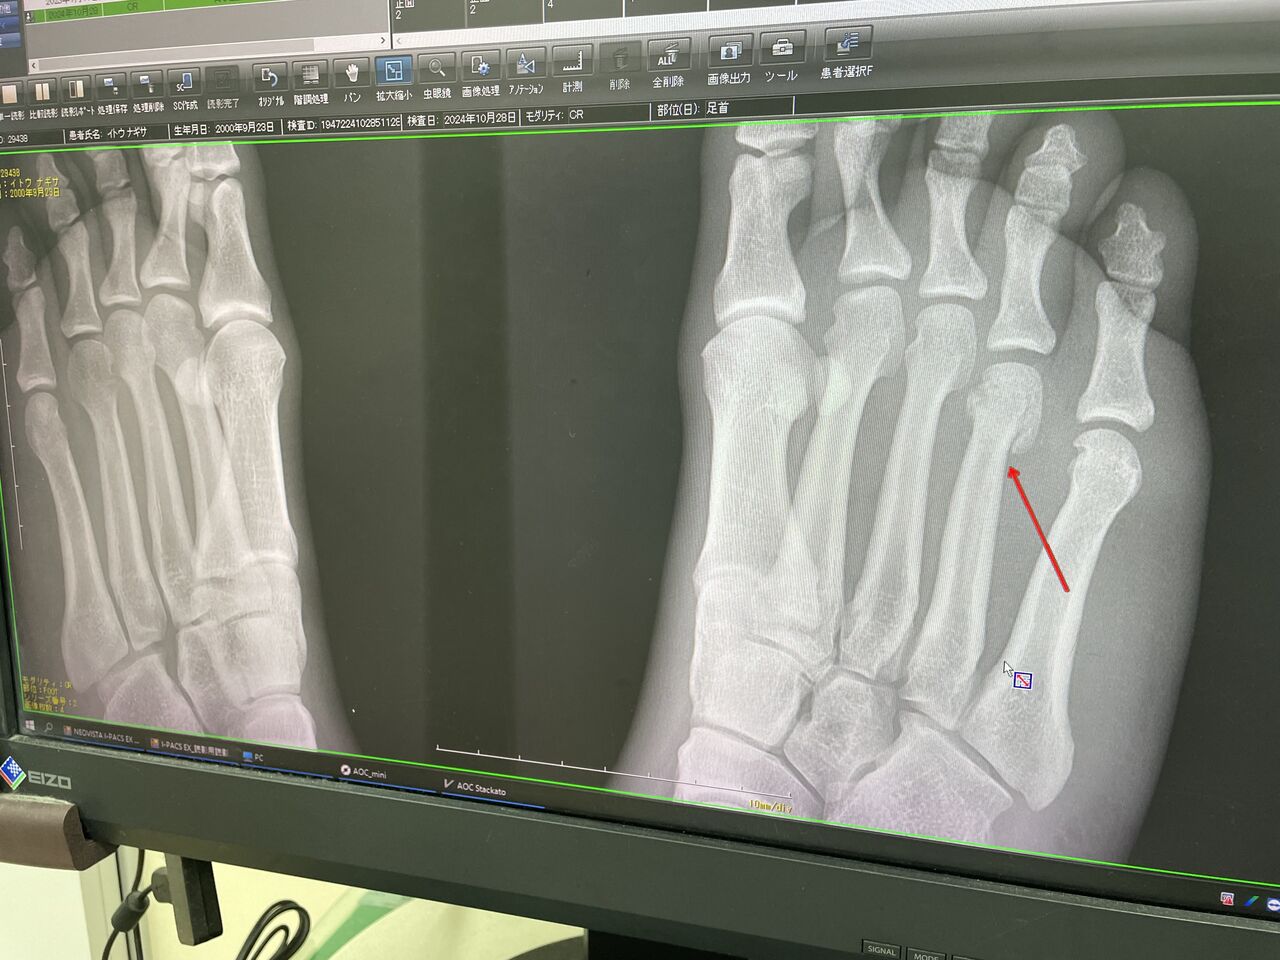

某高校アスリート なんと

今年8月に 世界選手権優勝! 世界 1 獲得!

もちろん、日本選手権優勝!

全日本ランキング1位

国体は間に合わないけれど、アジア選手権は狙っていきます!